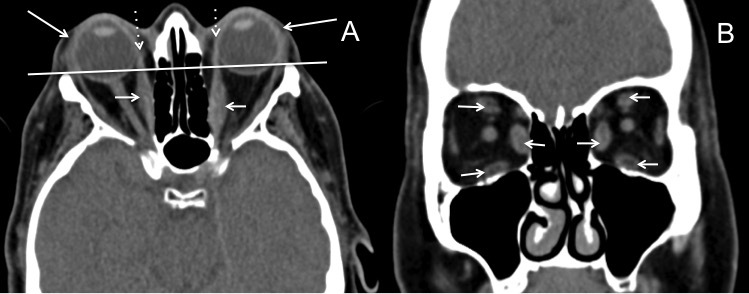

¿Cuáles son los hallazgos radiológicos en la TC de la obitopatía tiroidea?

¿Cuáles son los hallazgos radiológicos en la RM de la obitopatía tiroidea?